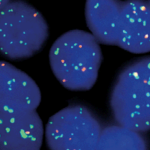

Quick Order Quick Order Name Email Address Company Address Catalog Number Quantity Message 14 + 5 = Submit Category Blocking Reagents Both Counterstain Country International US Detection Kit Detection Kit Detection kit 1-Step Polymer Kit Detection Kits - IHC 1-Step Polymer HRP Kits IHC AP Detection Kit IHC HRP Detection Kit IHC Mouse on Mouse 1-step Poly HRP kit New & Improved 1-Step Polymer HRP Kit IHC New & Improved Polymer HRP Kits IHC Polymer HRP Kits IHC Rapid Polymer HRP Kits IHC Double Staining eFISH Detection Kits ISH-Detection Kits Multiplex Detection Kits New & Improved Detection Kits Polymer HRP Kits IHC eFISH Enzymes for Tissue Processing Enzymes for Tissue Processing i6000 and Manual Instruments ISH Probes ISH-Detection Systems Links / Labels items-Manual Microscope Microchamber Slides & Coverslips for Xmatrx Microscope Slides & Accesories for i6000 and Manual Microscope Slides & Accessories Microscope Slides & Accessories miRNA Probes Primary Antibodies A Antibody Cocktail B C D E F G H I J K L M N O P R S T U V W Y Z Reagents Antigen Retrieval Solutions Blocking Reagents Blocking Reagents Buffers and Diluents Buffers eFSH Buffers ISH Buffers Counter Stains Detection Kit Dewaxing & Rehydration Reagents Diagnostic Antigen Retrieval Solutions eFISH Antigen Retrieval Solutions ISH Blocking Reagents ISH Enzymes Mounting Media eFISH Mount Media Nucleic Acid Retrieval Substrates & Chromogens ISH DAB replacements Slide Labels Vials Immunohistochemistry In situ Hybridization eFISH eFISH Probes eFISH Visualization Kits eFISH Visualization Kit Cyto eFISH Visualization Kit Histo Visualization Kit Ancillaries & Consumables Consumable Kits IHC Consumable Kits ISH Consumable Kits Counterstain and Mounting Media Counterstain Mounting PAP Pen Pipette Tips Reagent Vials & Accessories Reagent Vials & Accessories for i6000TM Diagnostics Reagent Vials & Accessories for Open system Automation Reagent Vials & Accessories for Xmatrx Elite Reagnet vials and accessories-1 Automation Detection Systems miRNA ISH Multiplexing & Double Staining Filters Sort results Reset Apply eFISH ETV6 Dual Color Break Apart Probe Select 10 tests (RTU)20 tests (RTU) Buy here eFISH ETV6 Dual Color Break Apart Probe Select 10 tests (RTU)20 tests (RTU) Buy here eFISH ETV6/RUNX1 Dual Color Dual Fusion Probe Select 10 tests (RTU)20 tests (RTU) Buy here eFISH ETV6/RUNX1 Dual Color Dual Fusion Probe Select 10 tests (RTU)20 tests (RTU) Buy here eFISH EWSR1 Dual Color Break Apart Probe Select 10 tests (RTU)20 tests (RTU) Buy here eFISH EWSR1 Dual Color Break Apart Probe Select 10 tests (RTU)20 tests (RTU) Buy here eFISH FGFR1/CEN 8 Dual Color Probe Select 10 tests (RTU)20 tests (RTU) Buy here eFISH FGFR1/CEN 8 Dual Color Probe Select 10 tests (RTU)20 tests (RTU) Buy here eFISH FGFR2/CEN 10 Dual Color Probe Select 10 tests (RTU)20 tests (RTU) Buy here eFISH FGFR2/CEN 10 Dual Color Probe Select 10 tests (RTU)20 tests (RTU) Buy here ‹ 1 … 83 84 85 … 146 ›